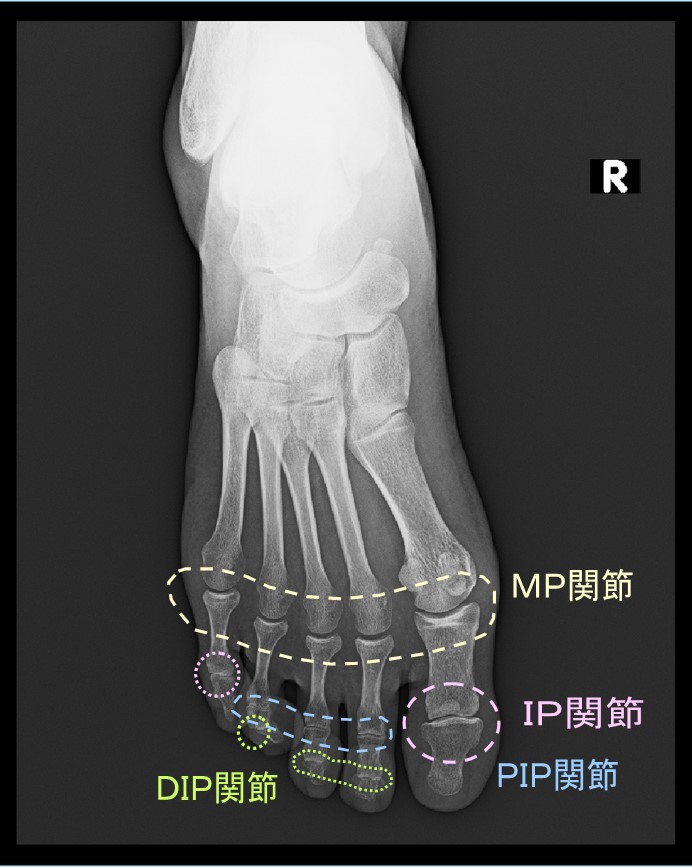

この記事ではそのような前足部の痛みについて提示したいと思います。まず、足指の関節の名称を提示します。第1足指と第5足指にはPIP関節がありません。足指は3つの骨(基節骨・中節骨・末節骨)から成り立っていますが、第1足指は元々中節骨が存在していません。第5足指では退化して中節骨がなくなってしまったために、2つの足指ではPIP関節がなくなり、IP関節という関節名となるのです。

足趾の関節の名称.jpg